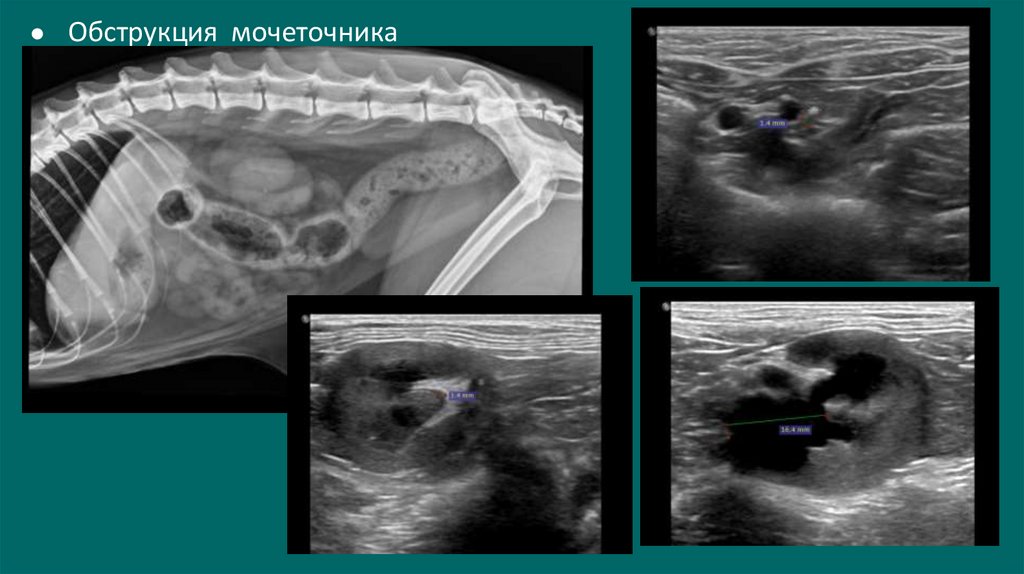

● Обструкция мочеточника

Обструкция мочеточника

УЗИ

38. УЗИ

Дилатация лоханки более 13 мм - обструкция

При диаметре лоханки более 8мм-высокая

вероятность обструкции